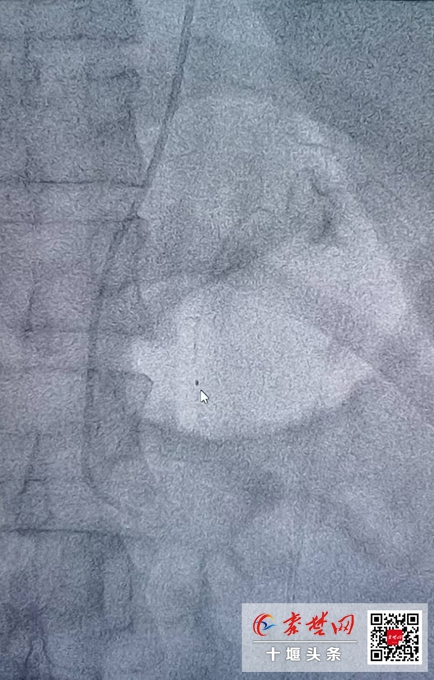

入院后,查肾上腺增强CT提示:双侧肾上腺结节。分侧肾上腺静脉取血(AVS)测量局部激素水平,证实夏女士为原发性醛固酮增多症,且左侧肾上腺醛固酮分泌为右侧80倍,左侧肾上腺为醛固酮分泌优势侧。确定必须对左侧肾上腺进行手术治疗。

术后,患者恢复良好,血压由术前的180/106mmHg迅速降至110/70mmHg,停止补钾后,多次复查血钾均为正常水平,低钾血症得到治愈,复查肝肾功能也均无损伤,醛固酮水平明显降低,大大减少患者心、脑、肾等器官损害,手术取得十分满意的效果。